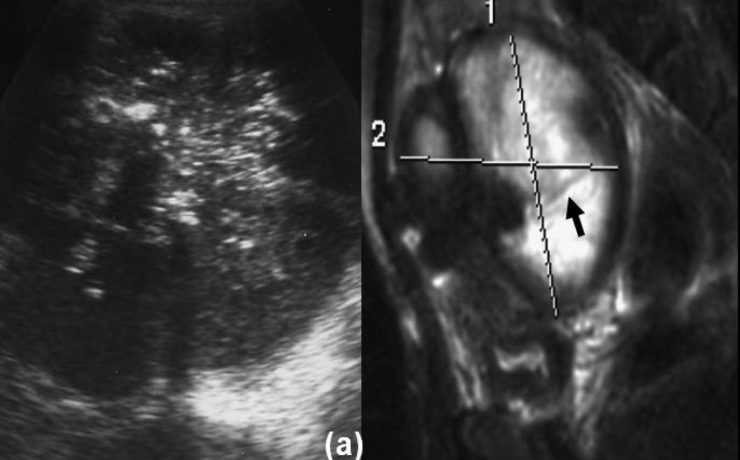

La ecografía del bazo.

La ecografía del bazo La ecografía del bazo es una parte fundamental del examen ecográfico completo, en el cual se evalúa el tamaño, forma, ubicación y parénquima del bazo, siendo necesario examinar y documentar estos aspectos detalladamente. Una de las principales ventajas de la ecografía es su amplia disponibilidad, bajo